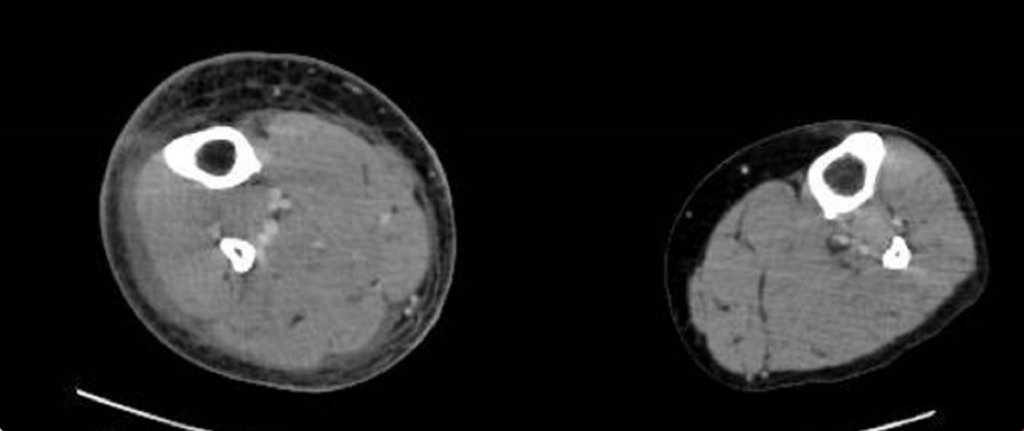

糖尿病の既往あり。昨日より右下腿の発赤、腫脹あり。本日痛みが強く歩けないため救急車にて救急外来を受診した。閉眼しており呼びかけに対して反応が鈍い。両側下腿の造影CT画像を示す

壊死性筋膜炎を疑う。速やかに血液培養をとり、広域抗菌薬の投与を開始するとともに、筋膜の試験切開を行う。